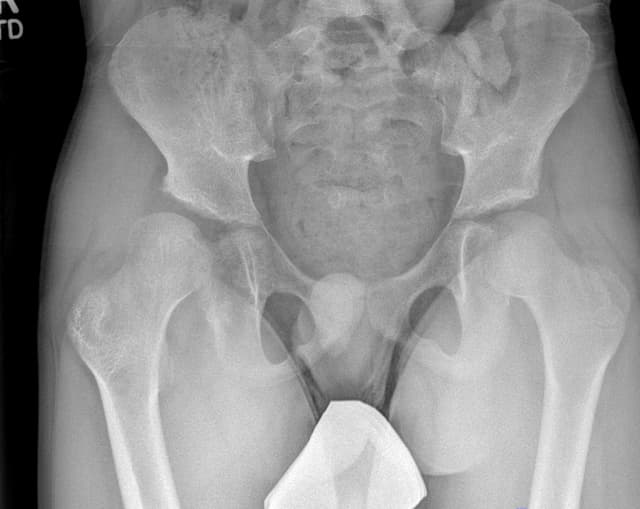

Varus Derotational Osteotomy of Proximal Femur

Rachel Thompson